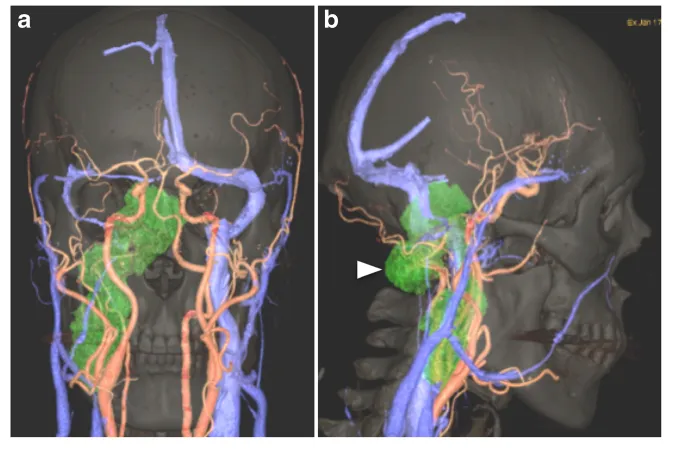

累及或延伸至岩骨的病变,由于位置深在、解剖结构复杂,手术挑战巨大。复杂的颈静脉孔区肿瘤,如较大的软骨肉瘤,可向前、向上延伸至岩尖。...